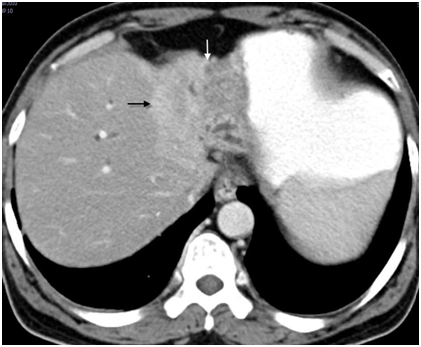

Liver parenchymal involvement adjacent to the mass lesion was present in 60(50.00%) patients (Figure 5). Liver invasion was present in 39(41.48%) patients, and 21(91.30%) patients in periductal-infiltrating and mass-forming tumor respectively. None of the patient of intraductal-growing tumor showed liver invasion. Seventy five(62.50%) patients had atrophy of the lobe, out of which 45(60.00%) patients had left lobe atrophy and 30(40.00%) patients had right lobe atrophy(either anterior or posterior segment or both). Lobar atrophy was present in one(33.33%), three(23.07%), 24(75.00%), 29(74.35%), and 18(54.54%) patients in Bismuth-Corlette type I, II, IIIa, IIIb, and IV respectively (Figure 6). Lobar atrophy was present in 56(59.57%) patients, 18(78.26%) patients, and 1(3.33%) patient in periductal-infiltrating, mass-forming, and intraductal-growing tumor respectively.

Figure 5 Type IV hilar cholangiocarcinoma - Infiltrating tumor (white arrow) involving the portal vein, its bifurcation and branches (black arrows) indicative of inoperable disease.

Portal vein involvement was subcategorized as involvement of the main vein, left branch, right branch, and anterior and posterior division of right branch (Figure 5). In 91(75.83%) patients, the portal vein was involved (Table 5A & Table 5B). In 27 out of 32 patients of type IIIa, portal vein was involved. Ipsilateral(right side) branch involvement was seen in 24 cases whereas contralateral branch involvement was seen in two cases and main branch involvement was seen in one case without right branch invasion. In 32 out of 39 patients of type IIIb, left branch was involved and in two cases right branch was involved without left branch invasion. In type IV, invasion of main portal vein or it’s right or left branch, or all three were seen in 24 patients. Two patients of type I and only four patients of type II showed portal venous invasion. Portal vein involvement was present in 70(74.46%) patients, 20(86.95%) patients, and 1(33.33%) patient in periductal-infiltrating, mass-forming, and intraductal-growing tumor respectively. Either main hepatic artery or its branches were involved in 57(47.50%) cases. Inferior vena cava was found to be involved in six (05.00%) cases and hepatic veins were involved in 12(10.00%) cases. Out of 91 patients with portal vein involvement, differential enhancement of the lobes was seen in 44(48.35%) patients (Figure 6).